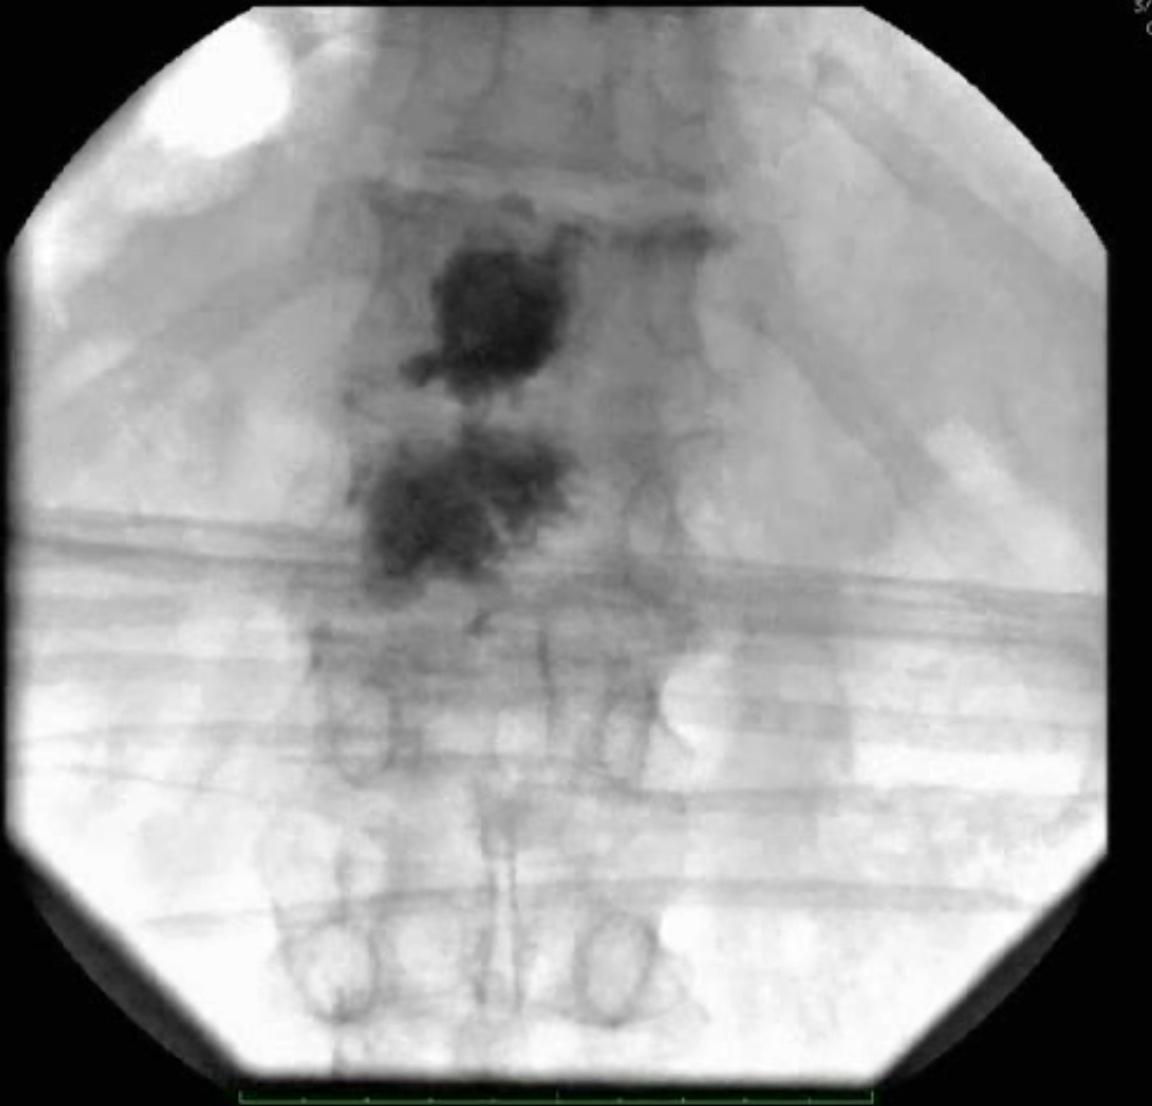

Als pedikulieren bezeichnet man den chirugrischen Vorgang transpedikulär in den Wirbelkörper zu gelangen, um beispielsweise eine Vertebroplastie, Kyphoplastie oder auch Spondylodese mittels Pedikelschrauben durchzuführen.

Das Pedikulieren kann je nach Ausstattung des Operationsraums mit einem oder zwei Fluoroskopiegeräte durchgeführt werden[^1].